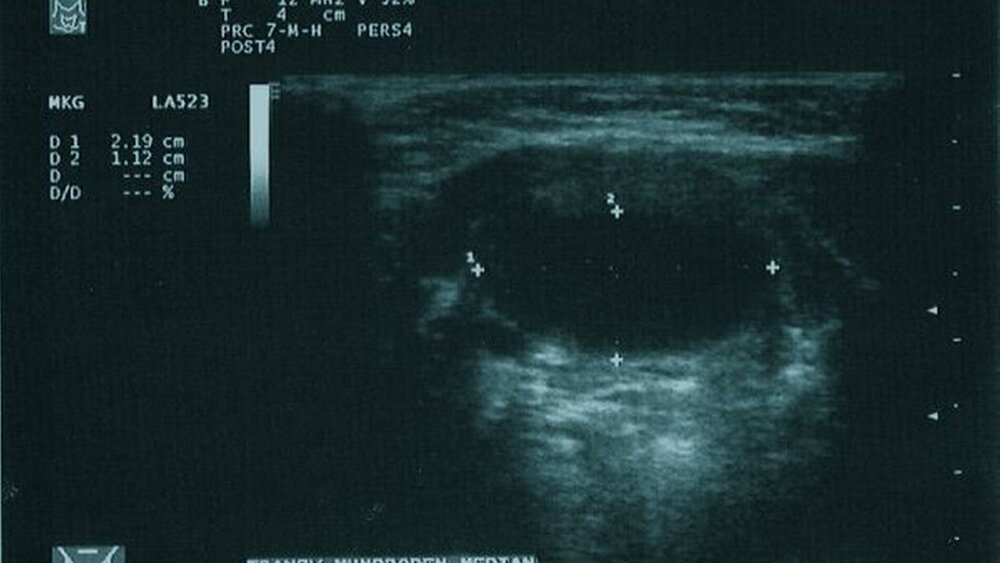

In der anschließend durchgeführten Sonografie des Halses kam eine 2,3 cm mal 2,4 cm mal 1,2 cm messende, hypodense und homogene Raumforderung mit dorsaler Schallverstärkung in der Medianebene des Halses oberhalb des Os hyoideum zur Darstellung (Abbildung 2).

Neben der Enukleation des zystisch imponierenden Gewebes wurde der mittlere Teil des kranialen Randes des Zungenbeins mit entfernt. Das entnommene Gewebe wurde histopathologisch begutachtet und die Verdachtsdiagnose bestätigt. Die beschriebene Grippesymptomatik, die den Verdacht auf einen möglichen Infekt gelenkt hatte, bestand höchstwahrscheinlich unabhängig vom Primärbefund. Nach einem dreitägigen stationären Aufenthalt konnte die Patientin bei Ausbleiben perioperativer Komplikationen in die ambulante Nachsorge entlassen werden. Ein Jahr postoperativ wurde die Patientin erneut in unserer Poliklinik aufgrund einer wiederaufgetretenen submentalen Schwellung vorgestellt. Wiederum zeigte sich eine prall-elastische, indolente Schwellung kaudal der Mundbodenmuskulatur. Die Ultraschalluntersuchung konnte erneut eine hypodense Raumforderung mit dorsaler Schallverstärkung mit einem Durchmesser von 1,2 cm mal 1,1 cm mal 0.9 cm Durchmesser nachweisen (Abbildung 5). Es musste daher von einem Rezidiv der medianen Halszyste ausgegangen werden. In der veranlassten Revisionsoperation konnte wieder ein zystischer Prozess entnommen werden. Die Histopathologie bestätigte den Verdacht eines Rezidivs. Zur Prophylaxe wurde in diesem Eingriff der gesamte mediane Anteil des Os hyoideum reseziert. Am zweiten postoperativen Tag konnte die Patientin in die ambulante Nachsorge entlassen werden.